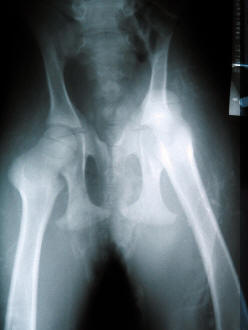

At the time of Diva's birth, she presented in a cushed position. (Her front legs where folded back to her chest and her rear legs where folded forward to her stomach) Once I knew Eve had been in labor for at least 1 hour and a second call to my vet showed he was still an hour away, I went in and felt Diva in the above described position. I followed her head down her neck, down her shoulder to each front leg which I pulled forward and out. Her head was then delivered and she started breathing but delivery stopped at her shoulders. I reached back in, felt her back feet at her sternum and pushed them back as far as I could. This ended up causing her rear legs to splay and lock against Eve's pelvis. Diva then stopped breathing so I had no choice but to pull her out. I felt two "pops" then Diva slid right out but her rear legs delivered folded backwards so that the insides of her thighs where now position to the outside and the outsides of her legs where now where her insides should have been. To understand this, follow the directions below. (Hold out your arms in front of you pointing at the computer screen with your palms facing each other, then swing your arms out and away from your body to each side as far as you can and imagine them continuing on to fold back behind you) Yea, OUCH! I had dislocated both the Right and the Left femoral heads from each asatabulum. (Pulled the balls out of the sockets) But that did not really matter since she was not breathing and I could not feel a heartbeat. I put her entire nose and mouth into my mouth and blew till I saw her chest expand. Then I thumped her chest with my fist. I kept breathing into her, waiting for her to take a breath on her own before each breath I gave her till finally she took one on her own. I rubbed her vigorously as she came back around. Once I knew she was back and going to stay, I turned my attention to her rear legs. I was able to put one back in but the other as you can see above was to severe for me to attempt. When I held Diva up by her sternum (chest) and gently lowered her to her feet, she could stand on her front legs but her rear legs would simply slide out to the sides, one going left, one going right resulting in her to "doing a spit". My vet, Dr. Miller arrived and took her to Catoosa Animal Medical Center where Dr. Marty Rodgers put Diva under with Iso and fixed her. The ligaments and tendons that where not torn, where stretched out so badly that Diva could not stand and her prognosis was poor. After consulting with a few Universities who could not offer any ideas as to how to bandage her, I came up with a solution of my own. Swim Diapers.